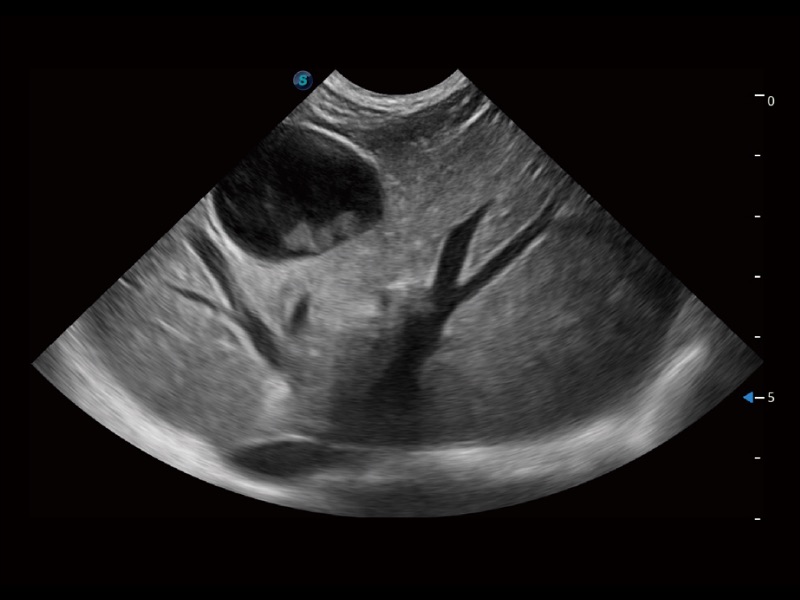

ProPet 70 进一步提升了微米成像算法,更加注重对基础原始图像的还原和保留,在有效减少斑点噪声、增强组织边界显示的同时,避免过度优化丟失真实的解剖信息。

一键自动识别膀胱壁及自动测量膀胱容积,不受膀胱形状和大小的限制,帮助医生快速精准获得测量的数据。